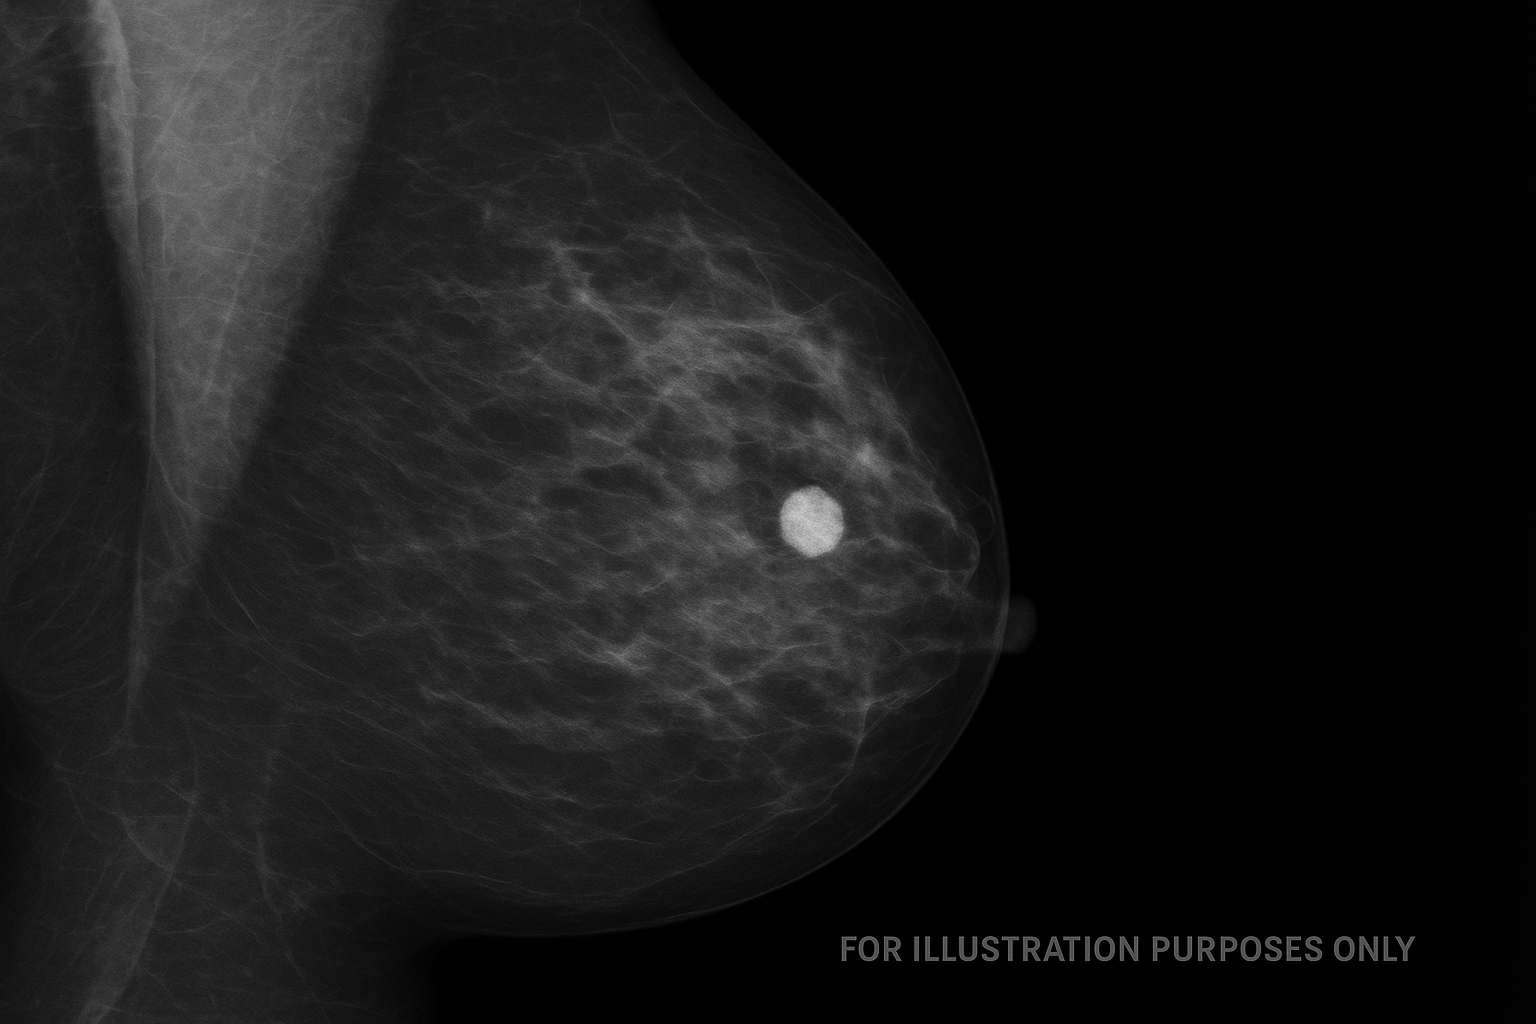

Ceļā uz gudrāku, precīzāku un efektīvāku veselības aprūpi – atskats uz starptautisku konferenci Rīgā par personalizētu vēža skrīningu

Starptautiska konference Rīgā par personalizētu vēža skrīningu pulcē Eiropas vadošos ekspertus